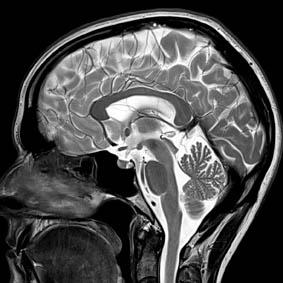

Images at 3T show crystal clarity, but its economics that will make what was once ultra high field into the clinical benchmark of MRI. Image provided by Siemens

So while 3T may not as yet have proven its heftier field strength to be a clinical advantage over the long-time king of MRI, its images are clearer and its price well within the reach of what buyers are used to paying.